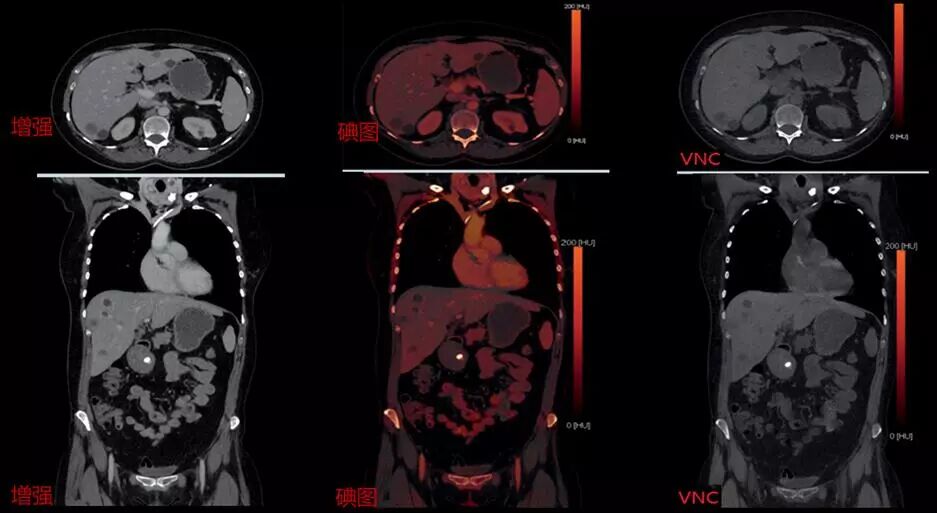

CT發(fā)展方向為宏觀的組織形態(tài)學(xué)診斷到微觀組織成分分析,因此雙能量成像也是各個廠家研發(fā)CT的方向之一,西門子獨創(chuàng)采用雙源雙能量成像技術(shù),同時具備4檔電壓組合:70/Sn150、80/Sn150、90/Sn150、100/Sn150可根據(jù)掃描部位更合理選擇電壓組合,因此可以做到更精準,更綠色,是業(yè)內(nèi)唯一可用于兒童的雙能量成像。

△高低能譜0重疊,精準分辨和量化物質(zhì)成分

△雙能量增強掃描可一次性獲得常規(guī)增強圖像、碘圖、及VNC